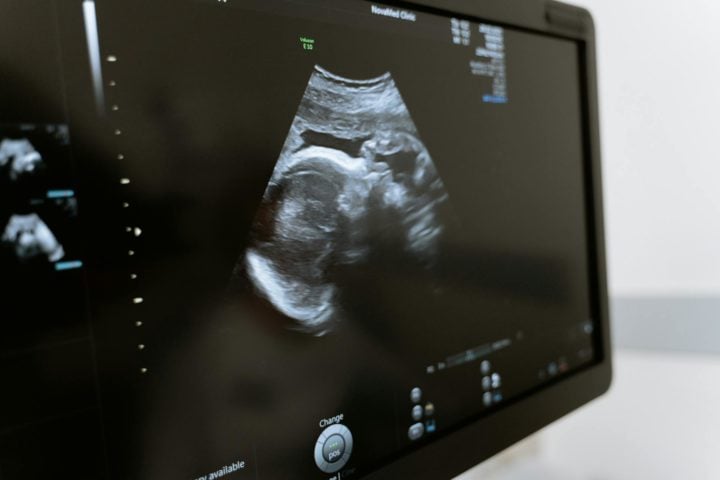

Mulher passa mais de 50 anos com feto calcificado na barriga